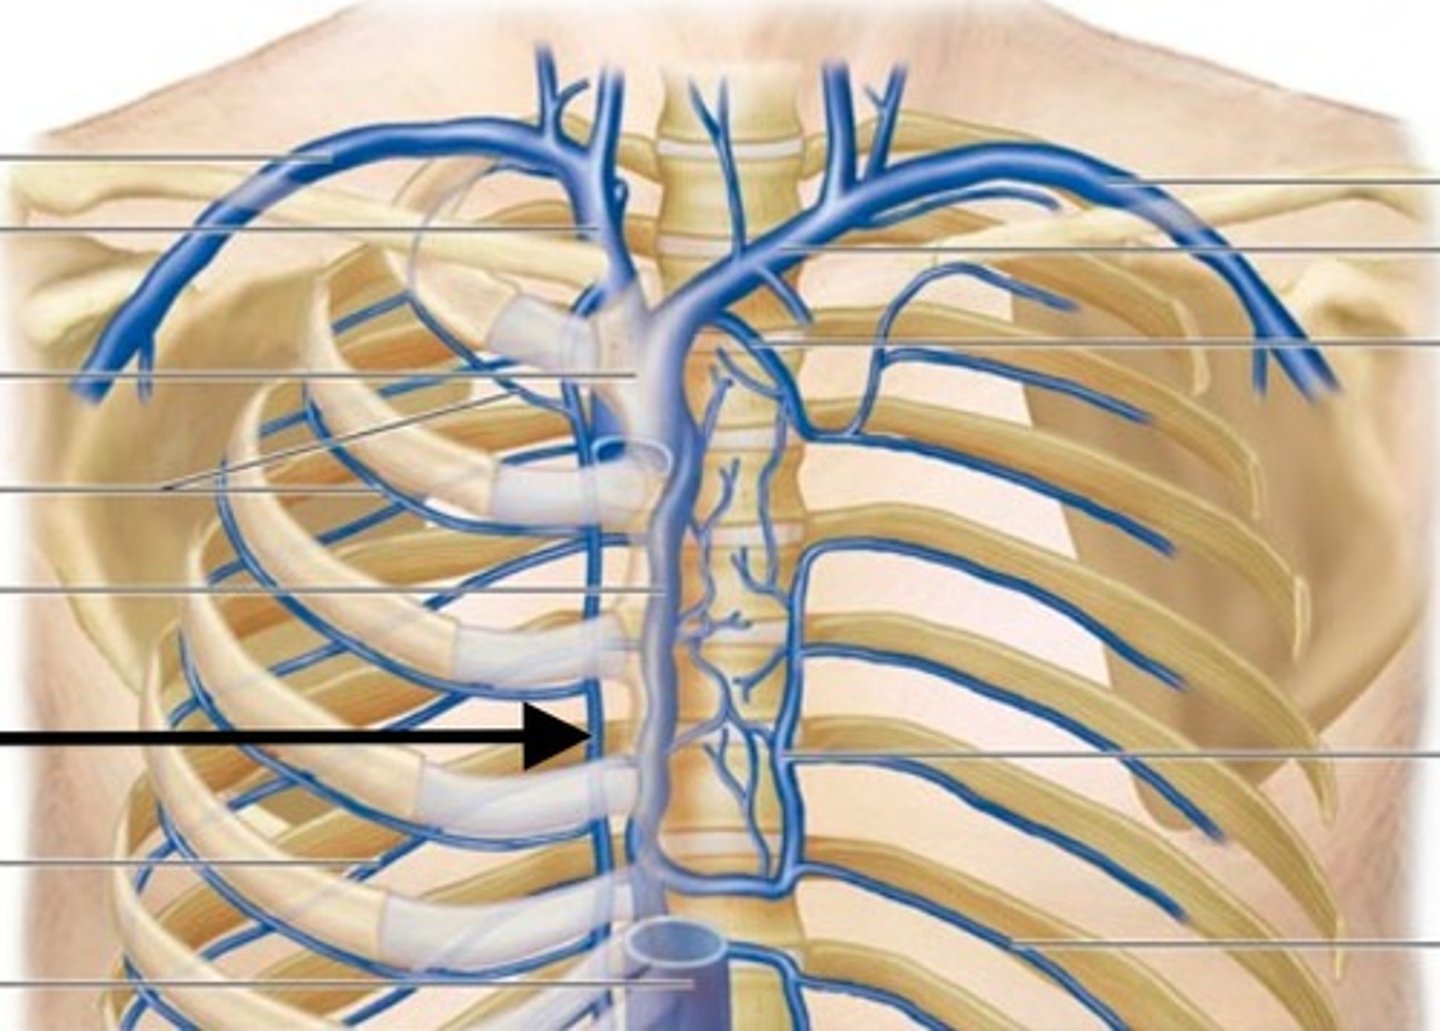

internal thoracic veins

What is this blood vessel?